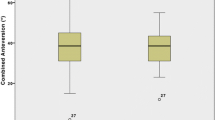

The mean native collo-trochanteric angle (49.1 ± 5.6°; range, 37.3–60.5°) did not differ significantly from the mean operative collo-trochanteric angle (48.8 ± 6.0°; range, 35.0–63.0°; p = 0.495, paired samples t-test). The correlation coefficient was 0.872 (p < 0.0001) and the values for bias and precision were calculated at 2.84 and 0.99, respectively (Fig. 4). The correlation coefficient, which described the degree of association between the native and operative collo-trochanteric angles, had 100% statistical power with the sample size of 59 hips Table 1.

Lesser trochanteric version

The mean lesser trochanteric version was 34.1 ± 3.0° (range, 30.1–39.0°; 95% confidence interval 33.33–34.87°) with 100% of values differing from the mean by less than 5°; this value showed 80% power for predicting the mean within 1° of error with the sample size of 59 hips.

ANOVA, with a post hoc Tukey honestly significant difference (HSD) test, revealed that neither gender nor the presence of a dysplastic/anatomically normal femur was significantly associated with discrepancies in the measurement of lesser trochanteric version. The mean lesser trochanteric version was 35.1 ± 3.0° (range, 30.1–39.0°) for women (n = 32 hips) and 32.9 ± 2.6° (range, 30.3–39.0°) for men (n = 27 hips). The mean lesser trochanteric version angle was 35.7 ± 3.0° (range, 31.1–39.0°) for dysplastic femora (n = 22 hips) and 33.2 ± 2.6° (range, 30.1–38.9°) for anatomically normal femora (n = 37 hips).